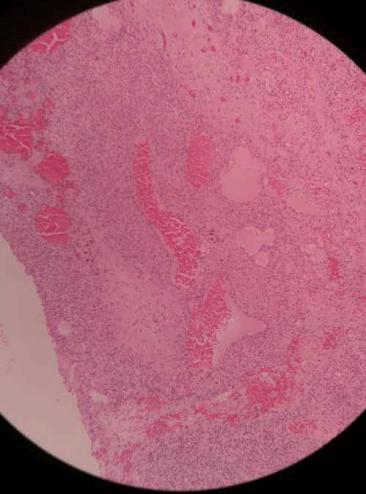

হিস্টোপ্যাথলজিকাল পরীক্ষা দ্বারা নির্ণয় করা হয়। এইচপিই বৃত্তাকার মোটা বা টাকু-আকৃতির কোষ সহ অসংখ্য স্ট্যাগহর্ন টাইপ ব্রাঞ্চিং ভাস্কুলার চ্যানেল দেখায়। টিউমারগুলি হিস্টোপ্যাথলজিকাল বৈশিষ্ট্য দ্বারা নিম্ন গ্রেড, মধ্যবর্তী গ্রেড এবং টিউমার সেলুলিটি, মাইটোটিক ফিগার, নিউক্লিয়ার অ্যাটিপিয়া, রক্তক্ষরণ এবং নেক্রোসিসের উপর ভিত্তি করে উচ্চ গ্রেডে পরিণত হতে পারে। উচ্চ-গ্রেডের ক্ষত দূরবর্তী মেটাস্টেসিসের সম্ভাবনা বেশি। এইচপিই-এর উপস্থিতিতে চিহ্নিত পরিবর্তনের কারণে, এইচপিসিগুলিকে গ্লোমাস টিউমার, অ্যাঞ্জিওসারকোমা, ফাইব্রাস হিস্টিওসাইটোমা, লিম্ফোমা, হেমেনজিওএন্ডোথেলিওমা এবং স্কোয়ানোমা হিসাবে ভুল নির্ণয় করা যেতে পারে। মাথা এবং ঘাড়ের টিউমারের 2005 WHO শ্রেণীবিভাগ অনুসারে, সাইনোনাসাল এইচপিসিগুলিকে গ্লোমাস টিউমারের সাথে তাদের মিলের কারণে গ্লোম্যানজিওপেরিসাইটোমা হিসাবে উল্লেখ করা যেতে পারে। ইমিউনোহিস্টোকেমিস্ট্রি ভিমেন্টিন ইতিবাচকতা দেখায়। খুব কমই তারা মসৃণ পেশী অ্যাক্টিন, ডেসমিন এবং S-100 ইতিবাচকতা দেখাতে পারে।